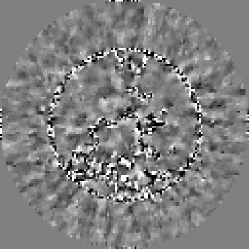

where is the reconstruction matrix described in Section 2, and is again the reconstructed image covariance matrix. Inspecting this expression for the image covariance matrix, it becomes obvious why the inversion of this matrix is nontrivial. has dimensionality , where is the number of pixels in the reconstructed image. Further, various components of the matrix such as the matrix representing the weighted back-projection step in the FBP algorithm make non-diagonal. Selected components of the matrices for the three reconstruction implementations considered here are shown in Fig. 2.

The reconstruction algorithm used was the FBP algorithm discussed in section 2. Projection data for the reference case was acquired over a full rotation at 1024 evenly spaced angles with 256 detector elements. The reconstruction was performed onto a pixel image grid with pixels roughly twice the size of a single detector element. The images were then cropped to a central pixel ROI, which was then displayed at magnification. Black and white lines were then superimposed on the image in order to aid the observers in localizing the signal at the center of the ROI. The reference images for the human and model observer study were reconstructed without regularization, i.e. with only the ramp kernel used for filtration. The ratio of the source-to-detector distance to the source’s radius of rotation was . The reference reconstructed signal is shown on the top left of Fig. 1. Visible artifacts in the reconstructed signal are a result of the discretization in the sinogram and image domains and the small size of the signal. This small signal size is desirable in this case because we can then expect greater variability in observer performance with respect to the reconstruction algorithm with the given noise model. The corresponding Hotelling template is pictured on the top right of Fig. 1.

As mentioned in Section 2, regularization can be performed in fan-beam FBP by applying a multiplicative apodization window to the ramp kernel in the Fourier domain. A case of heavy regularization is considered here, wherein a Hanning window with cutoff frequency equal to of the Nyquist frequency is used. For this case, we expect a drop in HO SNR relative to the reference (unmodified ramp kernel) case since this multiplicative window will place high-frequency components of the weighted projection data in the null-space of the reconstruction operator. The mean reconstructed signal and Hotelling template for the regularized study are shown in the middle row of Fig. 1.

Next, we considered the case of reconstruction onto pixels which are a factor of four larger than in the reference case, i.e. approximately eight detector bin widths square. Here, the expected loss in HO SNR arises from the fact that the reconstruction matrix has a more significant null-space due to the lower number of output image pixels relative to the number of input data elements. In other words, the matrix is now farther from being square, transforming an -element data vector to an -element image array where . The mean reconstructed signal and Hotelling template for the study involving larger pixels is shown in the bottom row of Fig. 1. Example pairs of images used in the regularization and large pixel studies are shown in the middle and bottom of Fig. 3.